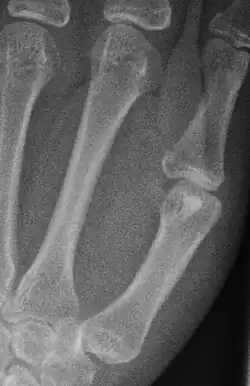

Das Enostom, auch Kompaktainsel, Enosteom oder engl. bone island genannt, ist eine Insel kortikalen Knochens im Markraum, in der Regel eines Röhrenknochens. Das Enostom ist ein häufiger, gutartiger Nebenbefund und stellt sich als meist ovoide oder runde Zone vermehrter Dichte (Sklerosierung) dar. In der Skelettszintigrafie ist dieser Befund negativ und kann so von osteoplastischen (knochenbildenden) Knochenmetastasen unterschieden werden.